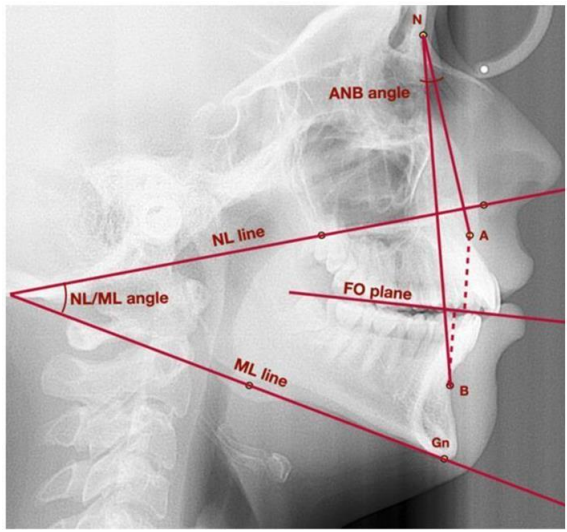

splint therapy and physiotherapy combined together significantly affect: the vertical and sagittal position of the mandible(fig.6), as well as the width of functional space between C1 and C2(fig.7) as the study of Marcin Derwich et al underlines17.

Figure 6.Lateral cephalogram with marked points, lines, and angles used to assess vertical and sagittal position of the mandible. A—point A; ANB—angle between lines NA and NB; B—point B; Gn—gnathion; FO plane—functional occlusal plane; ML—mandibular line; N—nasion; NL—nasal line; NL/ML—angle between lines: NL and ML17